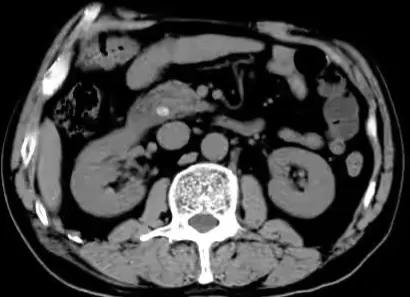

CT显示存在胆管结石

43岁的王先生是一名从事销售工作的职员,最近1个月反复“胃痛”,因为工作忙都是自己吃药对付。近3天发现小便像酱油一样,白眼球也有点发黄了,到医院检查发现胆管里面有一颗1cm大小的石头,胆囊也存在多发结石。我们给她做了腹腔镜下胆囊切除+胆管切开取石手术,术后很快尿色就正常了,肚子也没再疼。